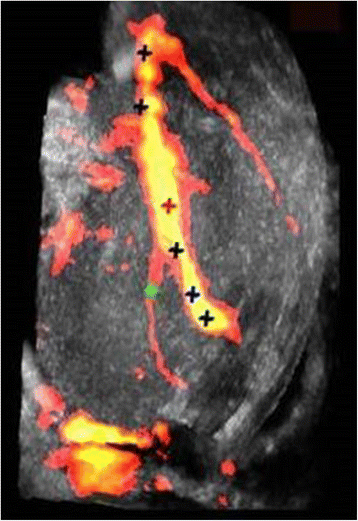

Similar to the in vitro DBAC treatment [1], an objective was a “two-button” treatment procedure available to the operator: Start D&L and Start Therapy. As depicted in Fig. 8, D&L included (a) B-mode and power Doppler mode acquisitions, (b) bleeder detection, (c) bleeder (or normal branch) characterization via resistive index, and therapy marker placement on the vessel target. Figure 9 shows a sample power Doppler image used for vascular branch characterization and bleeder (SFA branch) localization. If a DFA vessel segment was the designated target, the therapy marker was placed manually (since the DFA was not catheterized). The communication between D&L and therapy subsystems was also established at the end of the D&L sequence.

Image of limb vascularity in a test subject with SFA bleeder branch. Compound 3D power Doppler image with D&L automated algorithm-placed markers (crosses) denoting normal branches (bifurcations), vascular centerline markers, and the bleeder target (green cross), here 10 mm distal to the bleeder SFA branching point